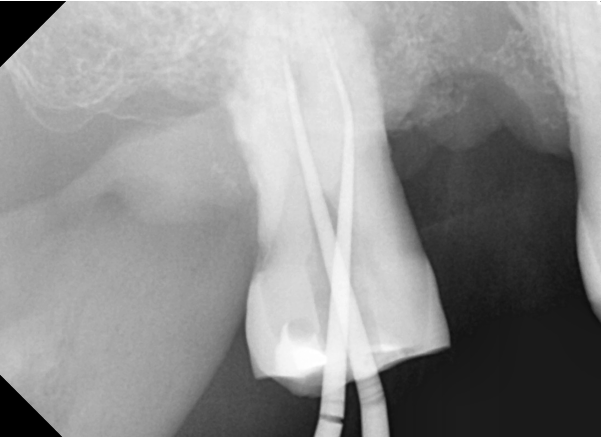

같은 부위에 있는 오른쪽 위 두번째 큰 어금니 신경치료를 시작하였습니다.

신경치료에 관한 부분은 다음 포스팅에 자세히 풀어보도록 하겠습니다 ^^

상악 임플란트의 경우 상악동이라는 공기주머니가 얇은 막으로 둘러싸고 있는데요

상악동을 다치게 하지 않으면서 임플란트를 잘 식립을 해야 합니다.

정확하고 안전하게 임플란트를 식립을 하기 위해

네비게이션 장치 제작을 위한 CT촬영과 구강내 scan을 하여

환자분이 수술 하시기전

제가 직접 자료를 통해 수술계획을 세워 준비를 합니다.